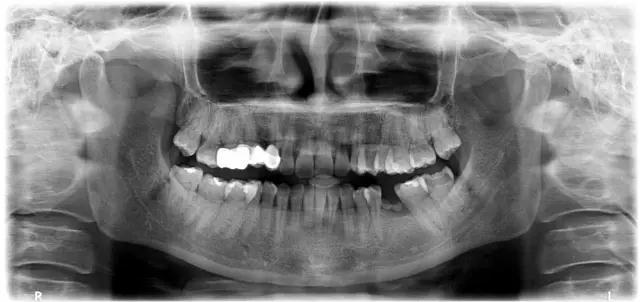

術前準備主要是醫生麵診,詢問既往病史和**訴求,然後做檢查,包括口腔全景片、頜骨CT等,查看**有無炎症以及牙槽骨條件等情況是否適合做種植牙。還要查血常規、凝血功能、血壓、血糖、乙肝5項、脈搏等,查看是否有影響種植牙的全身性疾病。

種植牙術前檢查